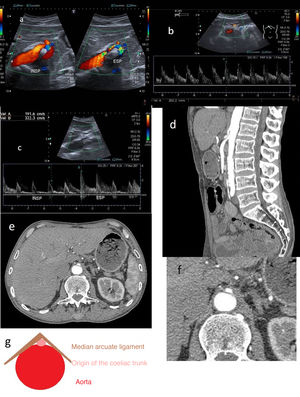

B-mode ultrasound has been proposed as a method for measuring the aortomesenteric angle, as well as calculating the ratio of the diameter of the dilated part of the LRV to the narrow part thereof and the distance between the aorta and the superior mesenteric artery, respectively. The cut-off points are an angle <25°, ratios >4.5 and a distance <8 mm, respectively. The difference in diameters between the right and left renal veins has also been used, though it is not a very widely accepted criterion (Fig. 8).

A) Calibre of the left renal vein (LRV) in the hilar region (before the angle): 12.2 mm. LRV calibre at the angle itself between the aorta (Ao) and the superior mesenteric artery (SMA): 1.5 mm. B) Decreased aortomesenteric angle at the LRV (20°). C) Increased LRV velocity at the aortomesenteric angle (106 cm/s). D) Normal LRV velocity prior to the angle (19 cm/s). E-G) Axial projections from contrast-enhanced computed tomography of abdomen in arterial phase (E) and portal phase (F and G). Image E shows a reduction in the calibre of the LRV as it passes through the aortomesenteric angle (yellow arrow). Image F shows slightly dilated gonadal veins (red arrow). Right parauterine varices are visible in Image G (blue arrow).

Doppler ultrasound measures the flow velocity of the LRV at the aortomesenteric angle, as well as the diameter and maximum flow velocity in the renal vein before and after it passes through the aortomesenteric angle, with a sensitivity of 78% and a specificity of 100%.

A maximum speed of the renal vein at the angle greater than 100 cm/s is considered abnormal (non-essential criterion). A distal-to-proximal ratio greater than 5 is diagnostic for this syndrome (Fig. 8C).